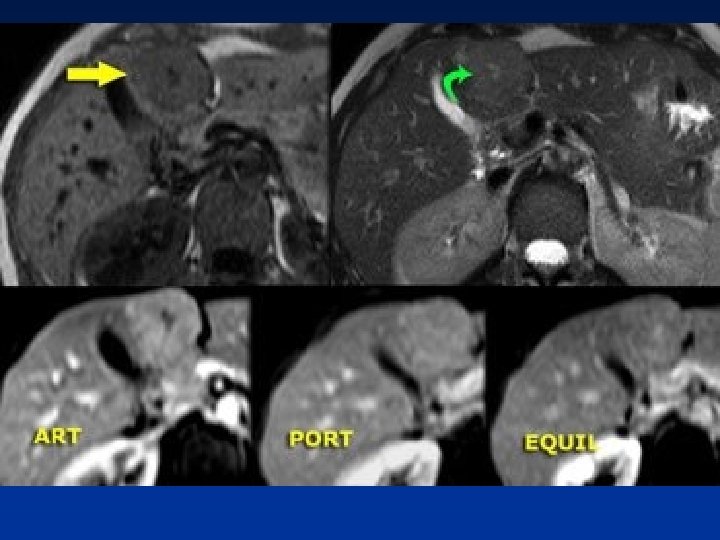

• In the arterial phase we see two hypervascular lesions. Now do not just concentrate on the images, where you see the lesions best. You have to look at all the other images, because they give you the clue to the diagnosis. The upper images show a lesion that is isodens to the liver on the NECT. In the arterial phase there is enhancement, but not as dense as the bloodpool. In the portal venous phase the lesion is again isodense to the surrounding liver parenchyma and you can't see it. If you only had the portal venous phase you surely would miss this lesion. The lower images show a lesion that is visible on all images. You see it on the NECT and you could say it is hypodens compared to the liver. Does this help you? No, not in the least. However if you look at the bloodpool, you will notice that on all phases it is as dense as the bloodpool. So we have a HCC in the right lobe on the upper images and a hemangioma in the left lobe on the lower images. The key is to look at all the phases.